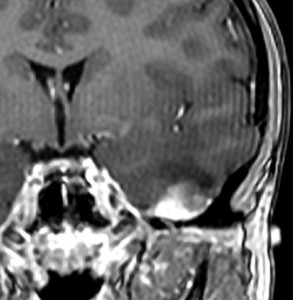

7才の時に音読でつかえるようになり,眼で何かを追っているような欠伸発作(左側頭葉てんかん)を繰り返すようになり,強直間代発作を生じて腫瘍が発見されました。下側頭回底面の皮質に発生した境界明瞭な腫瘍であり,周囲に脳浮腫を伴っています。T2強調画像で線維成分の多い硬い部分は低信号に,軟らかい部分はやや高信号となり,ガドリニウムでheterogenousに増強されます。グレード1の神経節膠腫としては非典型的な画像所見で術前診断は難しいもので,PXA pleomorphic xanthoastrocytoma も疑いました。もちろん治療としては開頭手術での全摘出です。術後に発作は消失しています。